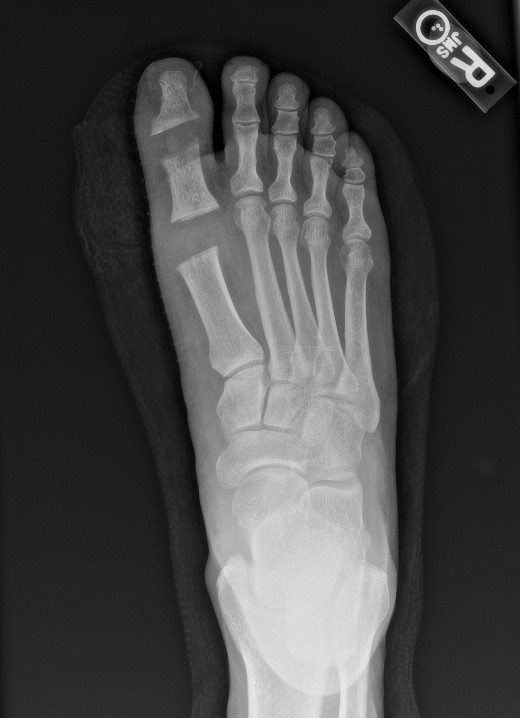

We ordered lab work including complete blood count (CBC), basic metabolic panel (BMP), erythrocyte sedimentation rate (ESR), C-reactive protein (CRP), and uric acid, all of which were unremarkable. Radiographs of the right foot demonstrated nonspecific subcutaneous edema, degenerative joint disease, and diffuse osteopenia, but were otherwise unremarkable. After a lengthy discussion of the risks and benefits, we obtained consent for joint aspiration. Using aseptic technique, an 18-gauge needle on a 5cc syringe aspirated the right hallux interphalangeal joint, which revealed chalky-white, gritty, crystals and blood-tinged synovial fluid. We replaced the syringe with the needle still in place intraarticularly and injected 0.5cc of dexamethasone sodium phosphate (10mg/mL). The patient tolerated the procedure well with no complications. The joint fluid aspirated was sent for culture and sensitivity testing as well as crystal analysis.

The patient was seen in the Emergency Department and presented with a heart rate of 101 beats per minute, blood pressure of 152/92 mmHg, and afebrile. Labs obtained demonstrated leukocytosis and neutrophilia. Radiographs obtained of the right foot were again unremarkable. The patient was admitted for sepsis and septic arthritis and started on intravenous vancomycin and cefepime. Blood cultures were obtained at time of admission.

Subsequent magnetic resonance imaging (MRI) of the right foot demonstrated small effusions of the first metatarsal head with underlying bone marrow edema and enhancement. There was also low T1 signal along the medial cortex and subcortical marrow. Additionally, the MRI showed erosions on the plantar aspect of the head of the hallux proximal phalanx with bone marrow edema and enhancement. These MRI findings were suggestive of osteomyelitis.